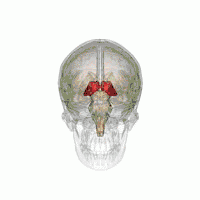

Таламус

![]() Таламус человека на МРТ-снимке, отмечен стрелкой | |

Тала́мус, иногда — зри́тельные бугры (лат. thalamus; от др.-греч. θάλαμος «комната, камера, отсек») — отдел головного мозга, представляющий собой большую массу серого вещества, расположенную в верхней части таламической области промежуточного мозга хордовых животных, в том числе и человека. Впервые описан древнеримским врачом и анатомом Галеном. Таламус — это парная структура, состоящая из двух половинок, симметричных относительно межполушарной плоскости. Таламус находится глубже структур большого мозга, в частности коры или плаща. Под таламусом расположены структуры среднего мозга. Срединная (медиальная) поверхность обеих половинок таламуса одновременно является верхней боковой стенкой третьего желудочка головного мозга[1][2][3].

Таламус расположен вблизи центра мозга и входит в число структур таламической области промежуточного мозга. Он залегает под структурами большого мозга, но возвышается над структурами среднего мозга. Восходящие аксоны, исходящие из нейронов ядер таламуса, формируют пучки миелинизированных нервных волокон. Эти пучки нервных волокон обильно проецируются на различные области коры больших полушарий головного мозга во всех направлениях. Медиальная поверхность обеих половинок таламуса одновременно является верхней частью боковой стенки третьего желудочка головного мозга. Она соединена с соответствующей медиальной поверхностью противоположной половинки таламуса плоской полосой белого вещества. Эта полоса представляет собой пучок миелинизированных нервных волокон и называется межталамическим сращением, или промежуточной массой третьего желудочка, или срединной комиссурой (срединной спайкой) таламуса.